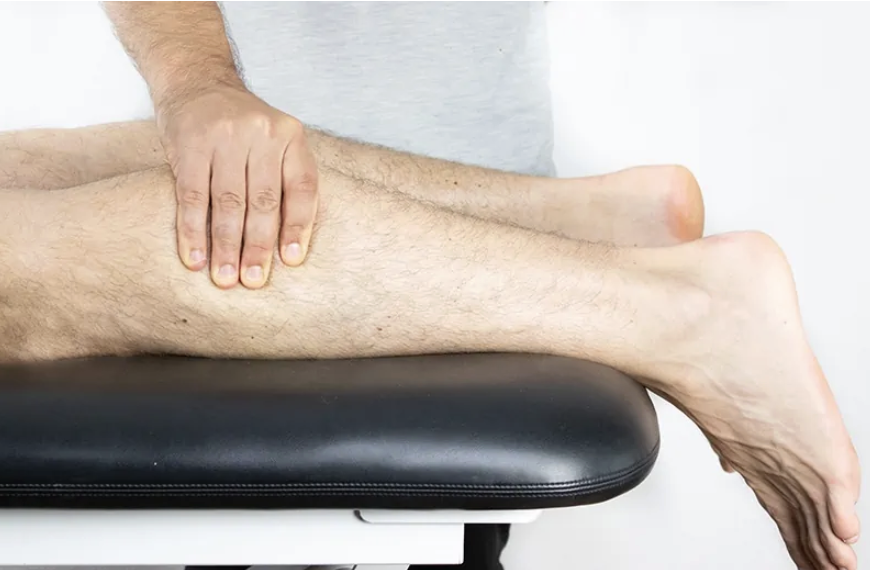

Fractura del tendón de aquiles “Weekend warrior”

Exploración física

• Signo de Thompson

• Defecto palpable “hachazo”